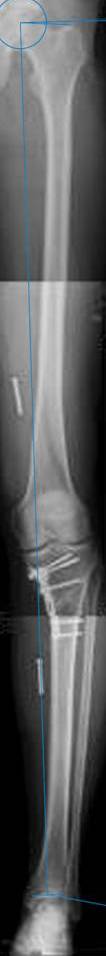

картинки оперированного пациента 40 лет, травма в 2006 году.

оперирован 06.11.2009г - корригирующая остеотомия большеберцовой кости.

Согласен с Вами, эта "скажем" не высокая остеотомия

нужно было выше.....

Я картинку собрал с некоторыми погрешностями, если провести отвес от центра вращения головки бедра до середины голени (на пациенте),то имеется небольшой вальгус (гиперкоррекция)конечно она (гиперкоррекция) не достигает 10 гр, но 5 гр она достигает.

Уважаемый д-р Батал Шушания,

К сожалению, не очень удачный пример. Если верить Р-граммам, имеет место быть дисплазия мыщелков бедренной кости с наклоном суставной линии. Это уже создает сложности получения хороших отдаленных результатов. Кроме того, по классике, необходима гиперкоррекция с созданием вальгуса 7-10 градусов для максимальной разгрузки медиального отдела КС. Если верить укладке, то линия сустава имеет четкий варусный наклон, поэтому результат операции м.б. кратковременным. В этих случаях показана двойная остеотомия бедра и тибии.

Впечатление искажает неправильная укладка.

Если сделать правильно, то видно, что бедренная кость в порядке, а цель остеотомии (низкой, кстати), не достигнута вовсе.

Сохраняется варус. Для того, чтобы создать вальгусную гиперкоррекцию, не моделируя при этом откровенный Х голени, можно сделать медиализирующую остеотомию.